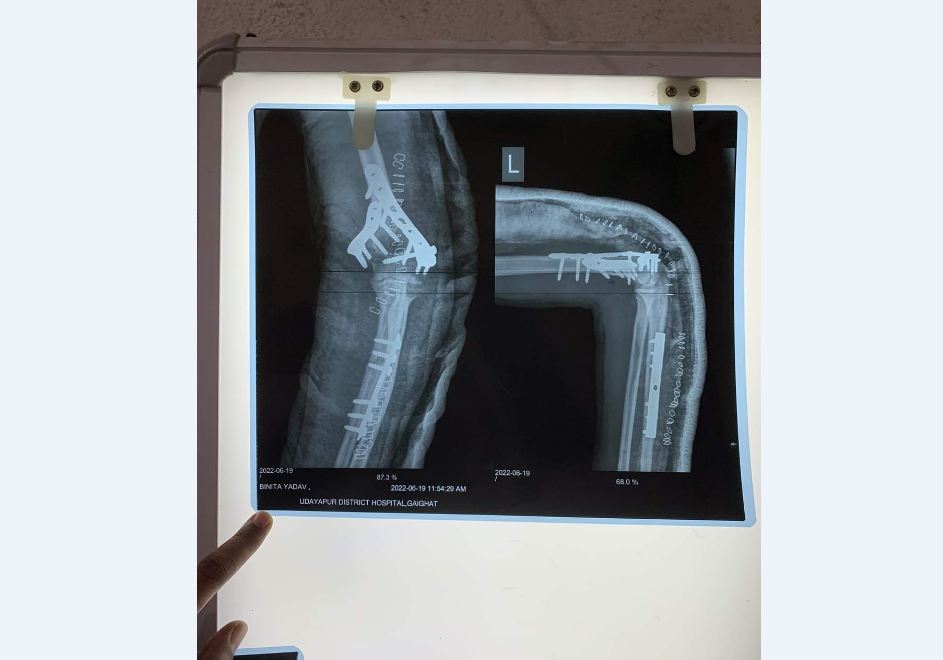

काठमाडौं- उदयपुर अस्पताल, गाईघाटमा हाडजोर्नीको ५३ औँ शल्यक्रिया सफलतापुर्वक सम्पन्न भएको छ। आईतबार सिरहा जिल्ला मिर्चैयाकी १७ वर्षिया विनिता यादवको कुहिनाको हड्डी भाँचिएको शल्यक्रिया सफलतापुर्वक भएसँगै ५३ औ शल्यक्रिया सम्पन्न भएको हो।

हालसम्म भाँचिएको क्ल्याभिकलको, नलिखुट्टा फुटेको र भाँचिएको घुँडाको, दुबै हड्डीे भाँचिएको हातको अप्रेशन लगाएतका शल्यक्रियाहरु सफलतापूर्वक सम्पन्न भई केही बिरामीहरु निको समेत भईसकेको अस्पतालले जनाएको छ।